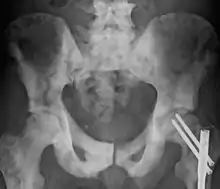

| Sclerosis of the bones of the pelvis due to prostate cancer metastases | |

Osteosclerosis can be detected with a simple radiography. There are white portions of the bone which appear due to the increased number of bone trabeculae.